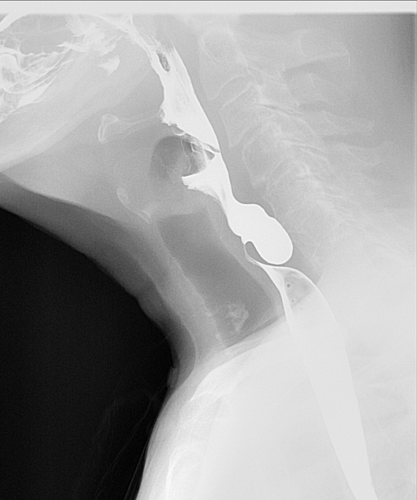

Pharyngeal pouch

Background: Regurgitation of foodstuff hours or days after eating, with or without dysphagia can be a symptoms of a pharyngeal pouch. There may be halitosis. Some complain of a “wet” sounding voice. This is a rare herniation of the pharynx where foodstuffs can accumulate.

Image of pharyngeal pouch

Figure – Lateral view on barium swallow